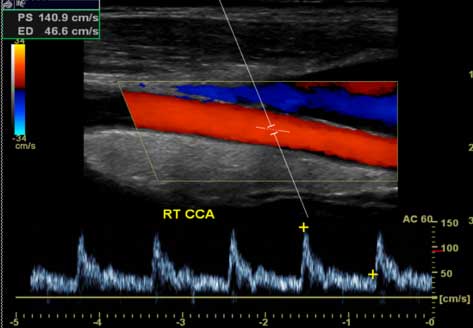

Right common carotid artery. Doppler wave form added at the bottom.

Note: Images are shown for illustrative purposes. Do not attempt to draw conclusions or make diagnoses by comparing these images to other medical images, particularly your own. Only qualified physicians should interpret images; the radiologist is the physician expert trained in medical imaging.